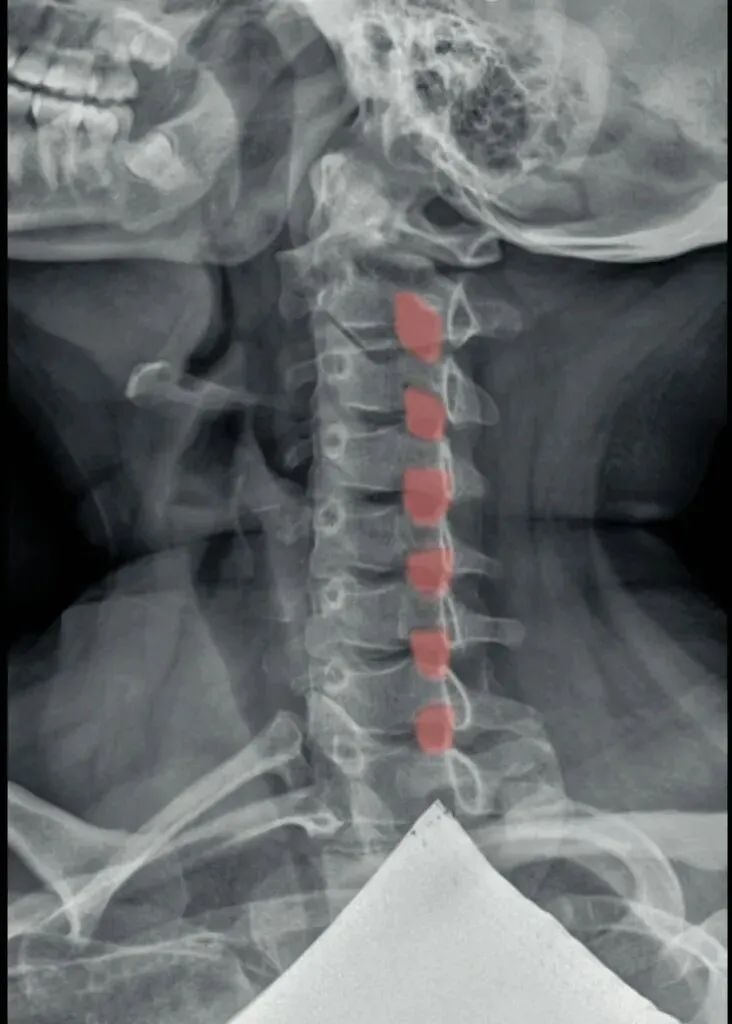

六旋指颈椎旋转,需结合颈椎正侧位观察。

颈椎正位主要观察棘突有没有偏歪,有没有在棘突中心轴线的连线上。

如果某一节椎骨的棘突中心点偏离,各棘突中心连线大于等于3毫米,则表示该节段颈椎有轴向旋转。

侧位主要观察椎体有没有双边征和关节突有没有双突征。

造成这两个征象的原因就是椎体后缘及双侧关节突没有完全重叠,摄影体位不标准时也会出现这种现象。所以我们要结合正侧位观察,如果正位没有出现某节段颈椎棘突偏移,但是侧位出现颈椎双凸或双边征时,大概率就是摄影体位不标准。反之正位能看到某节段颈椎棘突偏移,同时侧位能看到对应节段颈椎的双边或者双凸征时,基本可以确定椎体存在旋转。